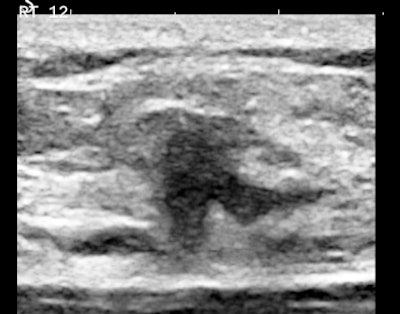

Figures 3A and 3B are the B-mode and simultaneous SWE of a follicular neoplasm of the thyroid. Notice how the elastogram indicates a cell population heterogeneity that is not visible in the original image.

![]() |

| Figures 3A and 3B. |

Homogeneous and heterogeneous are classic ultrasound image features. Perhaps ultimately, refining this descriptor and even quantifying it will be the most important role of SWE in practice.